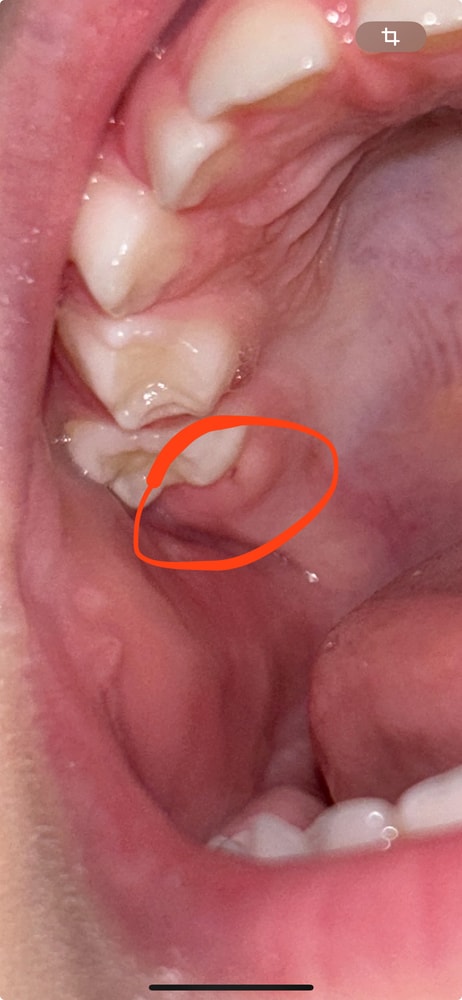

Вчера у дочки обнаружила опухшую десну, сегодня уже что-то похожее на зуб!

Нам 2 года 9 мес, все зубы вышли (всего 20 зубов)

Сегодня обнаружила, что режется что-то после второго моляра сверху 😳разве такое возможно?😁это что? Постоянный зуб? (Я фото закину в комментарии)

Девочки, у дочки после второго моляра какая-то припухлость (фото прикреплю). Вроде не беспокоит её, случайно увидела во время чистки зубов 😰

Кто сталкивался, что это может быть? Уехали ещё из города к родителям погостить и как обычно что-то да вылазит😰